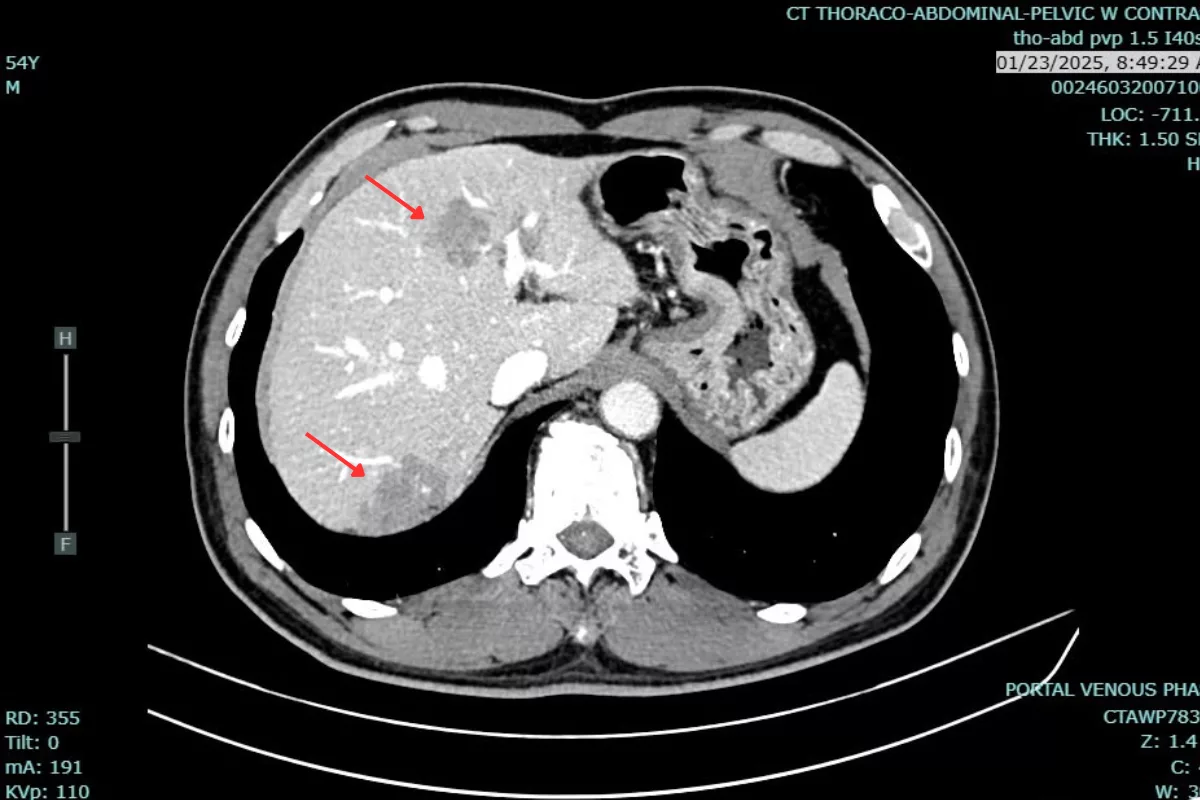

Dr. Bui Quang Loc reported:”The patient responded well to treatment. After the first cycle, some of the smaller liver lesions were no longer visible on post-treatment CT scans. After nearly a year, the largest liver lesion’s volume decreased from 78 mL to 27.26 ml. Liver metastases remained stable after treatment. Additionally, the patient’s CEA level dropped from 105.6 ng/ml to 33.6 ng/ml.”This patient’s treatment journey is a strong testament to the effectiveness of a personalized, multimodal approach in managing metastatic rectal cancer. The dedicated monitoring, tailored regimen adjustments, and close patient follow-up by the medical team at Hanoi French Hospital played a crucial role in not only controlling the disease but also improving the patient’s quality of life.